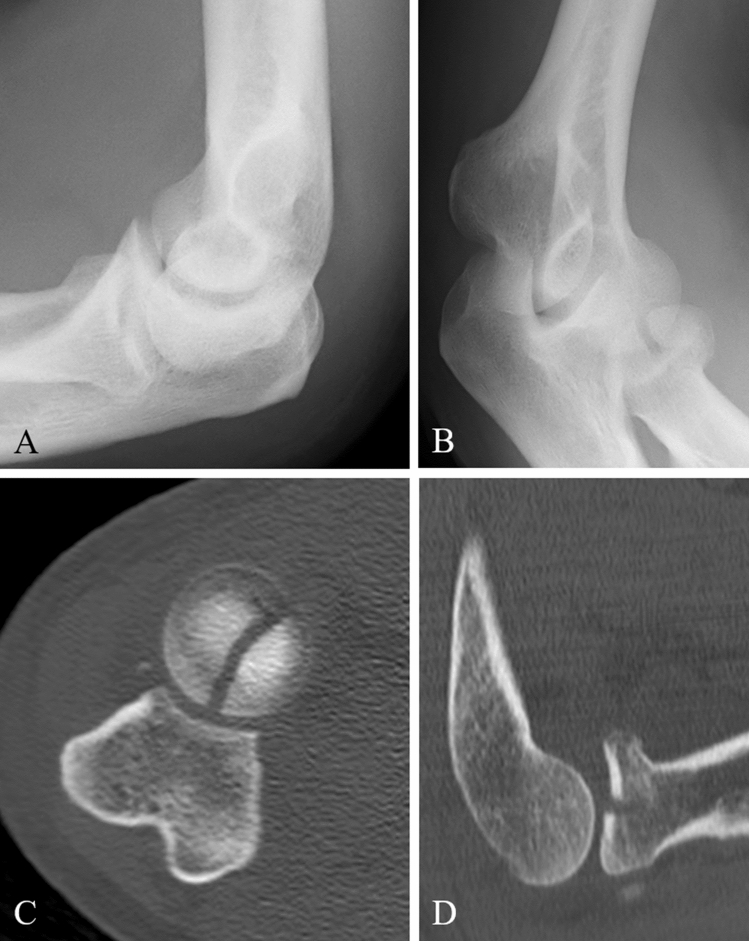

Fig. 4.

a, b Preoperative radiographs (anteroposterior and lateral) of a Mason type III fracture (Case 2). c CT-scan in axial view and d in sagittal view